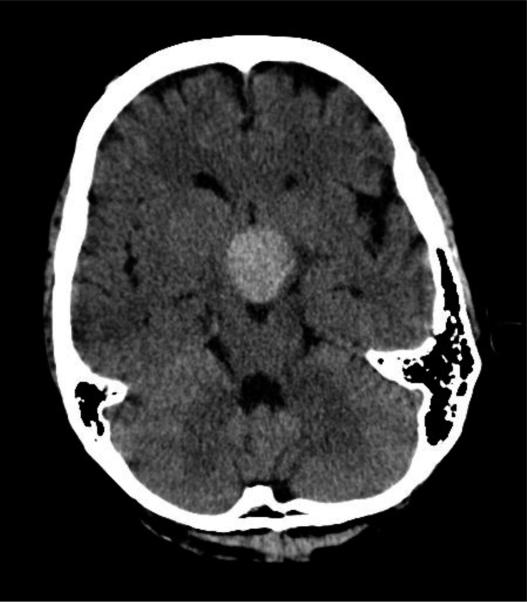

Incidence estimates for perioperative vision loss (POVL) after nonocular surgery range from 0.013% for all surgeries up to 0.2% following spine surgery. The most common neuro-ophthalmologic causes of POVL are the ischemic optic neuropathies (ION), either anterior (AION) or posterior (PION). We identified 111 case reports of AION following nonocular surgery in the literature, with most occurring after cardiac surgery, and 165 case reports of PION following nonocular surgery, with most occurring after spine surgery or radical neck dissection. There were an additional 526 cases of ION that did not specify if the diagnosis was AION or PION. We also identified 933 case reports of central retinal artery occlusion (CRAO), 33 cases of pituitary apoplexy, and 245 cases of cortical blindness following nonocular surgery. The incidence of POVL following ocular surgery appears to be much lower than that seen following nonocular surgery. We identified five cases in the literature of direct optic nerve trauma, 47 cases of AION, and five cases of PION following ocular surgery. The specific pathogenesis and risk factors underlying these neuro-ophthalmic complications remain unknown, and physicians should be alert to the potential for loss of vision in the postoperative period.